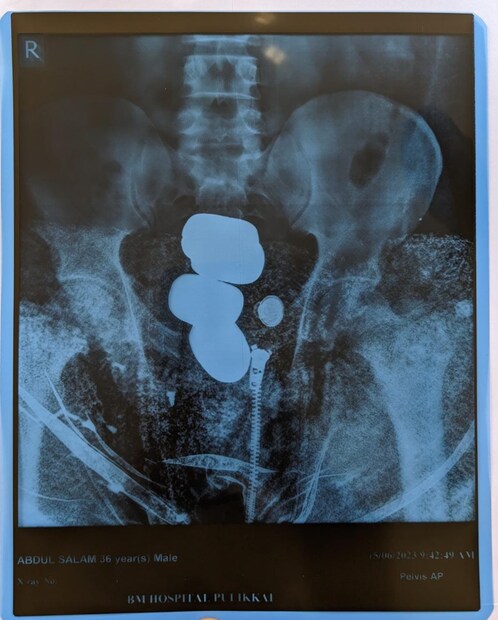

പൊന്നാനി സ്വദേശി അബ്ദുസലാം (36) ആണ് 1656 ഗ്രാം 24 ക്യാരറ്റ് സ്വര്ണ്ണം സഹിതം എയര്പോര്ട്ടിന് പുറത്ത് വെച്ച് പോലീസ് പിടിയിലായത്

ശരീരത്തിനുള്ളിൽ ഒളിപ്പിച്ചു കടത്തുവാൻ ശ്രമിച്ച ഏകദേശം 48 ലക്ഷം രൂപ വില മതിക്കുന്ന 855 ഗ്രാം മിശ്രിത രൂപത്തിലുള്ള സ്വർണം ആണ് കോഴിക്കോട് എയർ കസ്റ്റംസ് ഇന്റലിജൻസ് ഉദ്യോഗസ്ഥർ പിടികൂടിയത്. ഉമ്മർകോയ ശരീരത്തിനുള്ളിൽ ഒളിപ്പിച്ചുവച്ച നാലു ക്യാപ്സ്യൂളുകളിൽനിന്നും ആണ് കസ്റ്റംസ് ഈ സ്വർണ്ണമിശ്രീതം പിടിച്ചെടുത്തത്.